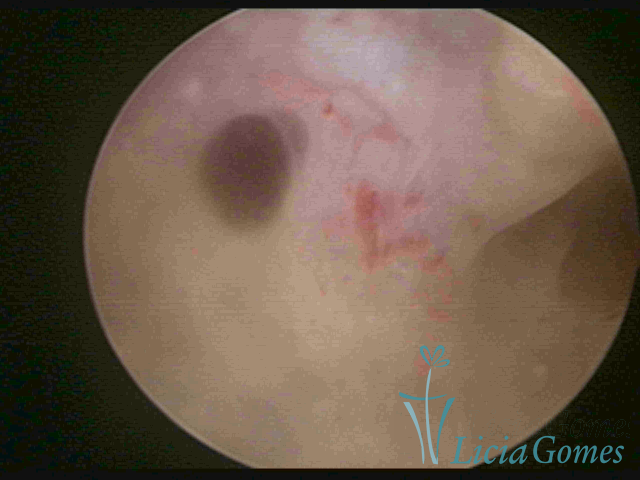

ADENOMIOSE

É a presença de tecido endometrial na camada muscular do útero

A vídeo-histeroscopia permite diagnosticar às lesões próximas às camadas miometriais superficiais, próximo ao endométrio visualizando lesões de coloração violácea, circunscritas, ou acastanhadas com conteúdo achocolatado.